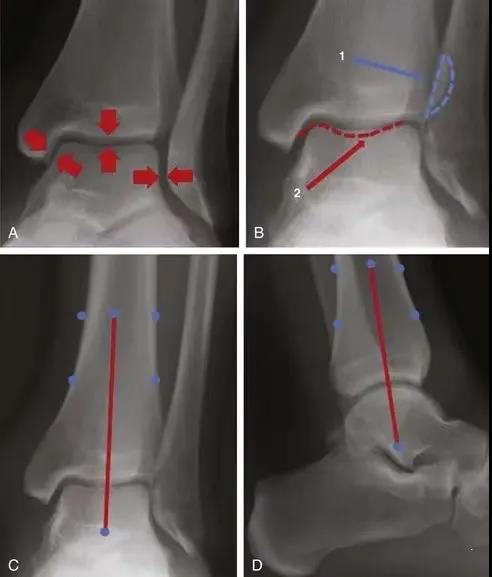

A,关节面应在整个关节中等距(箭头)。B,腓骨与远端胫骨(1)和后踝(2)关节。C和D,正侧位腿的中轴(红线)穿过穹顶的中心和距骨。